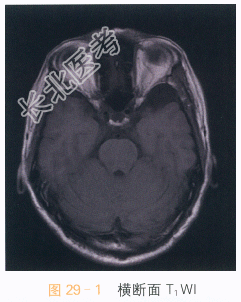

影像学资料如图29-1~图29-4所示。

读片分析:头颅横断面T₁WI、T₂WI见左侧中颅窝异常信号灶,呈长T₁WI、长T₂WI信号,边界清晰,左侧颞极受压,信号无明显异常改变;冠状面T₂WI及矢状面T₁WI亦可见左侧中颅窝长T₁WI、长T₂WI信号影,左侧颞极受压改变。结合患者病史,诊断为蛛网膜囊肿。